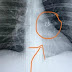

Um jardineiro de Cincinnati, Ohio, procurou o pronto-socorro de um hospital após sentir fortes e insistentes tosses, além de reclamar que “algo estava bloqueando as vias aéreas”. Os médicos o mandaram fazer um exame de raio-X acreditando que poderia ser uma pneumonia, entretanto a imagem mostrou que a causa do incômodo era na verdade um piercing de nariz que o paciente havia perdido há mais de cinco anos.

Joey Lykins, de 35 anos, acredita que o objeto de 0,6 polegadas embutido no seu lobo superior esquerdo do pulmão tenha sido inalado durante o sono. Ele afirma que o objeto de metal “sumiu” em uma manhã há cinco anos. Ao acordar, ele notou que o piercing não estava mais em seu nariz.